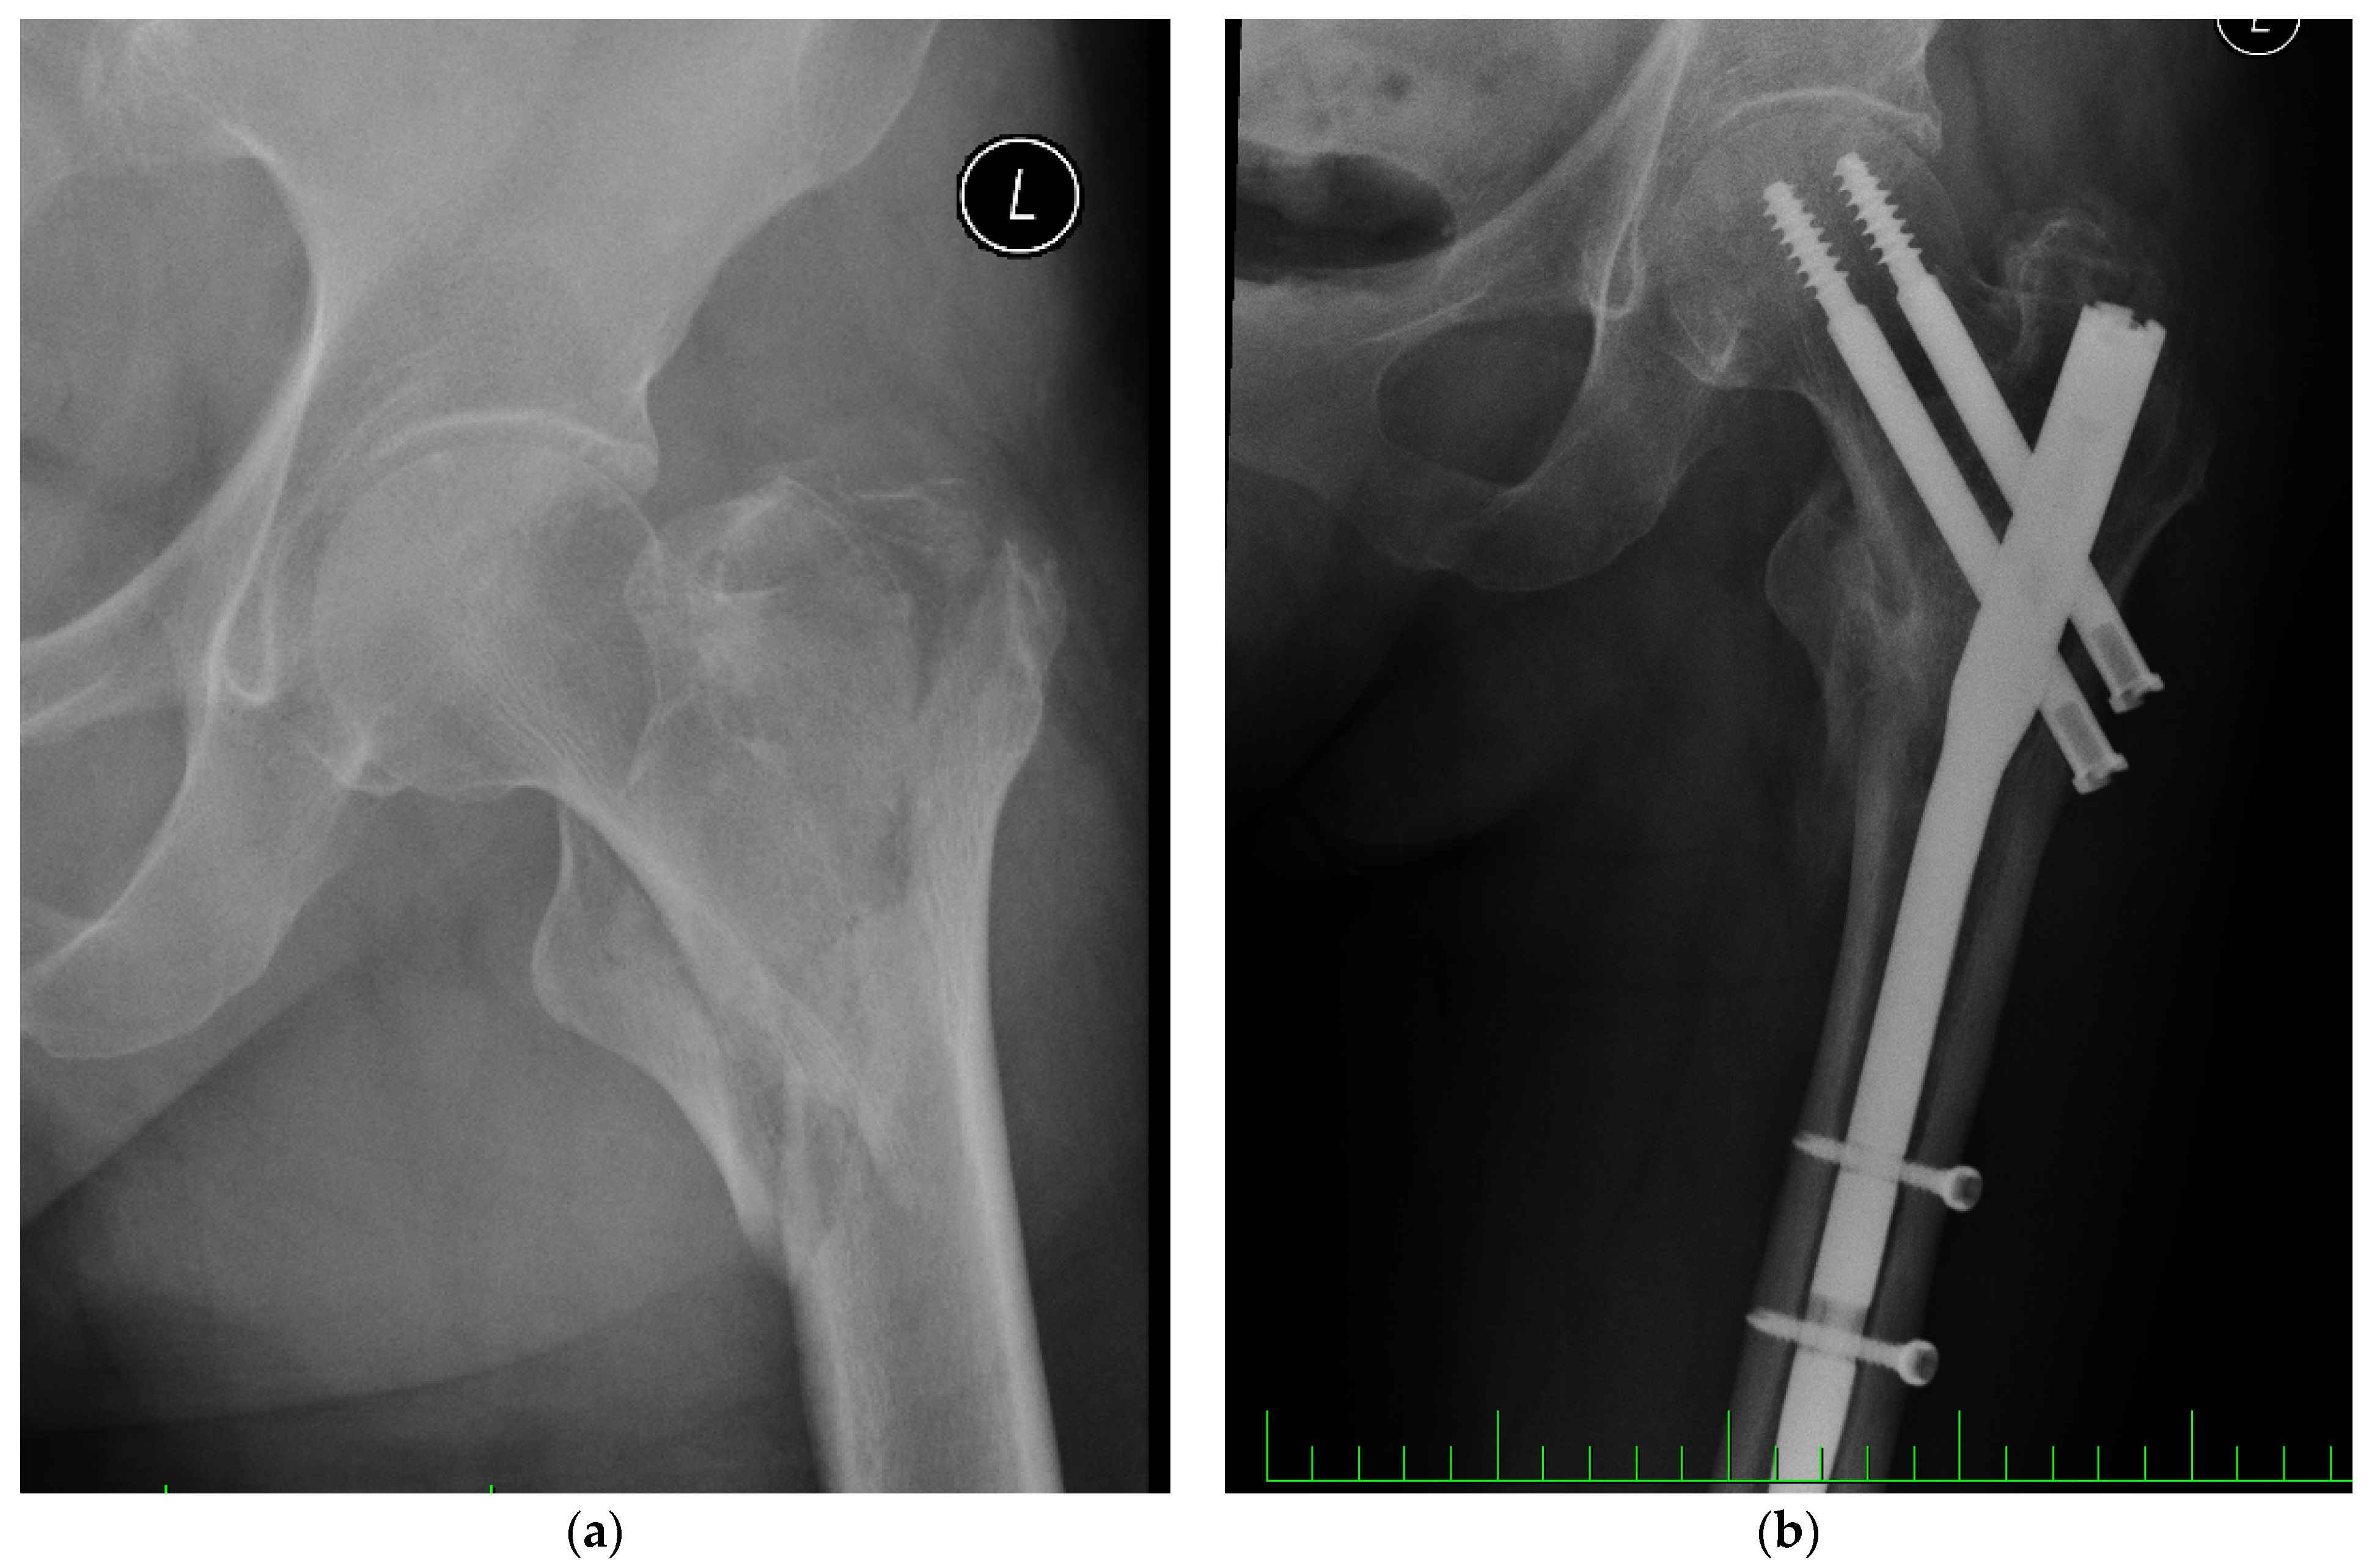

Biomechanical Assessment of Cannulated Nails for the Treatment of Proximal Femur Fractures

Frydrýšek, K.; Halo, T.; Čepica, D.; Machalla, V.; Šimečková, K.; Skoupý, O.; Madeja, R.; Havlíček, M.; Dostálová, K.; Trefil, A.; et al. Biomechanical Assessment of Cannulated Nails for the Treatment of Proximal Femur Fractures. Appl. Sci. 2022, 12, 7470. https://doi.org/10.3390/app12157470